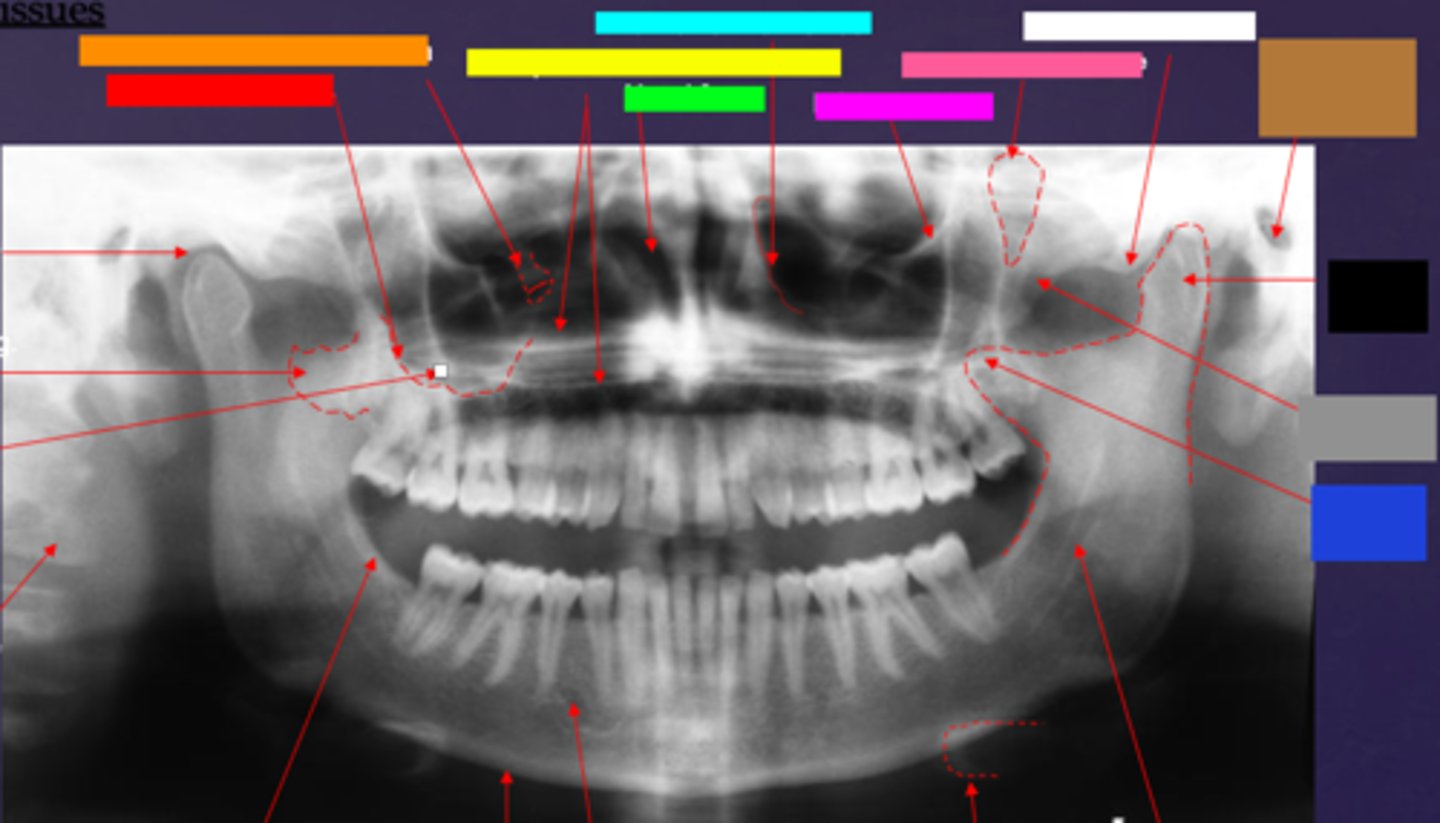

ID the hard tissue anatomy indicated by the arrow pointing from the orange box:

lateral pterygoid plate

ID the hard tissue anatomy indicated by the arrow pointing from the yellow box:

zygomatic process of maxilla

ID the hard tissue anatomy indicated by the arrow pointing from the green box:

cervical spine

ID the hard tissue anatomy indicated by the arrow pointing from the light blue box:

external oblique ridge

ID the hard tissue anatomy indicated by the arrow pointing from the hot pink box:

inferior boarder of the mandible

ID the hard tissue anatomy indicated by the arrow pointing from the pink/salmon box:

mental foramen

ID the hard tissue anatomy indicated by the arrow pointing from the black box:

inferior alveolar canal

ID the hard tissue anatomy indicated by the arrow pointing from the white box:

hyoid bone